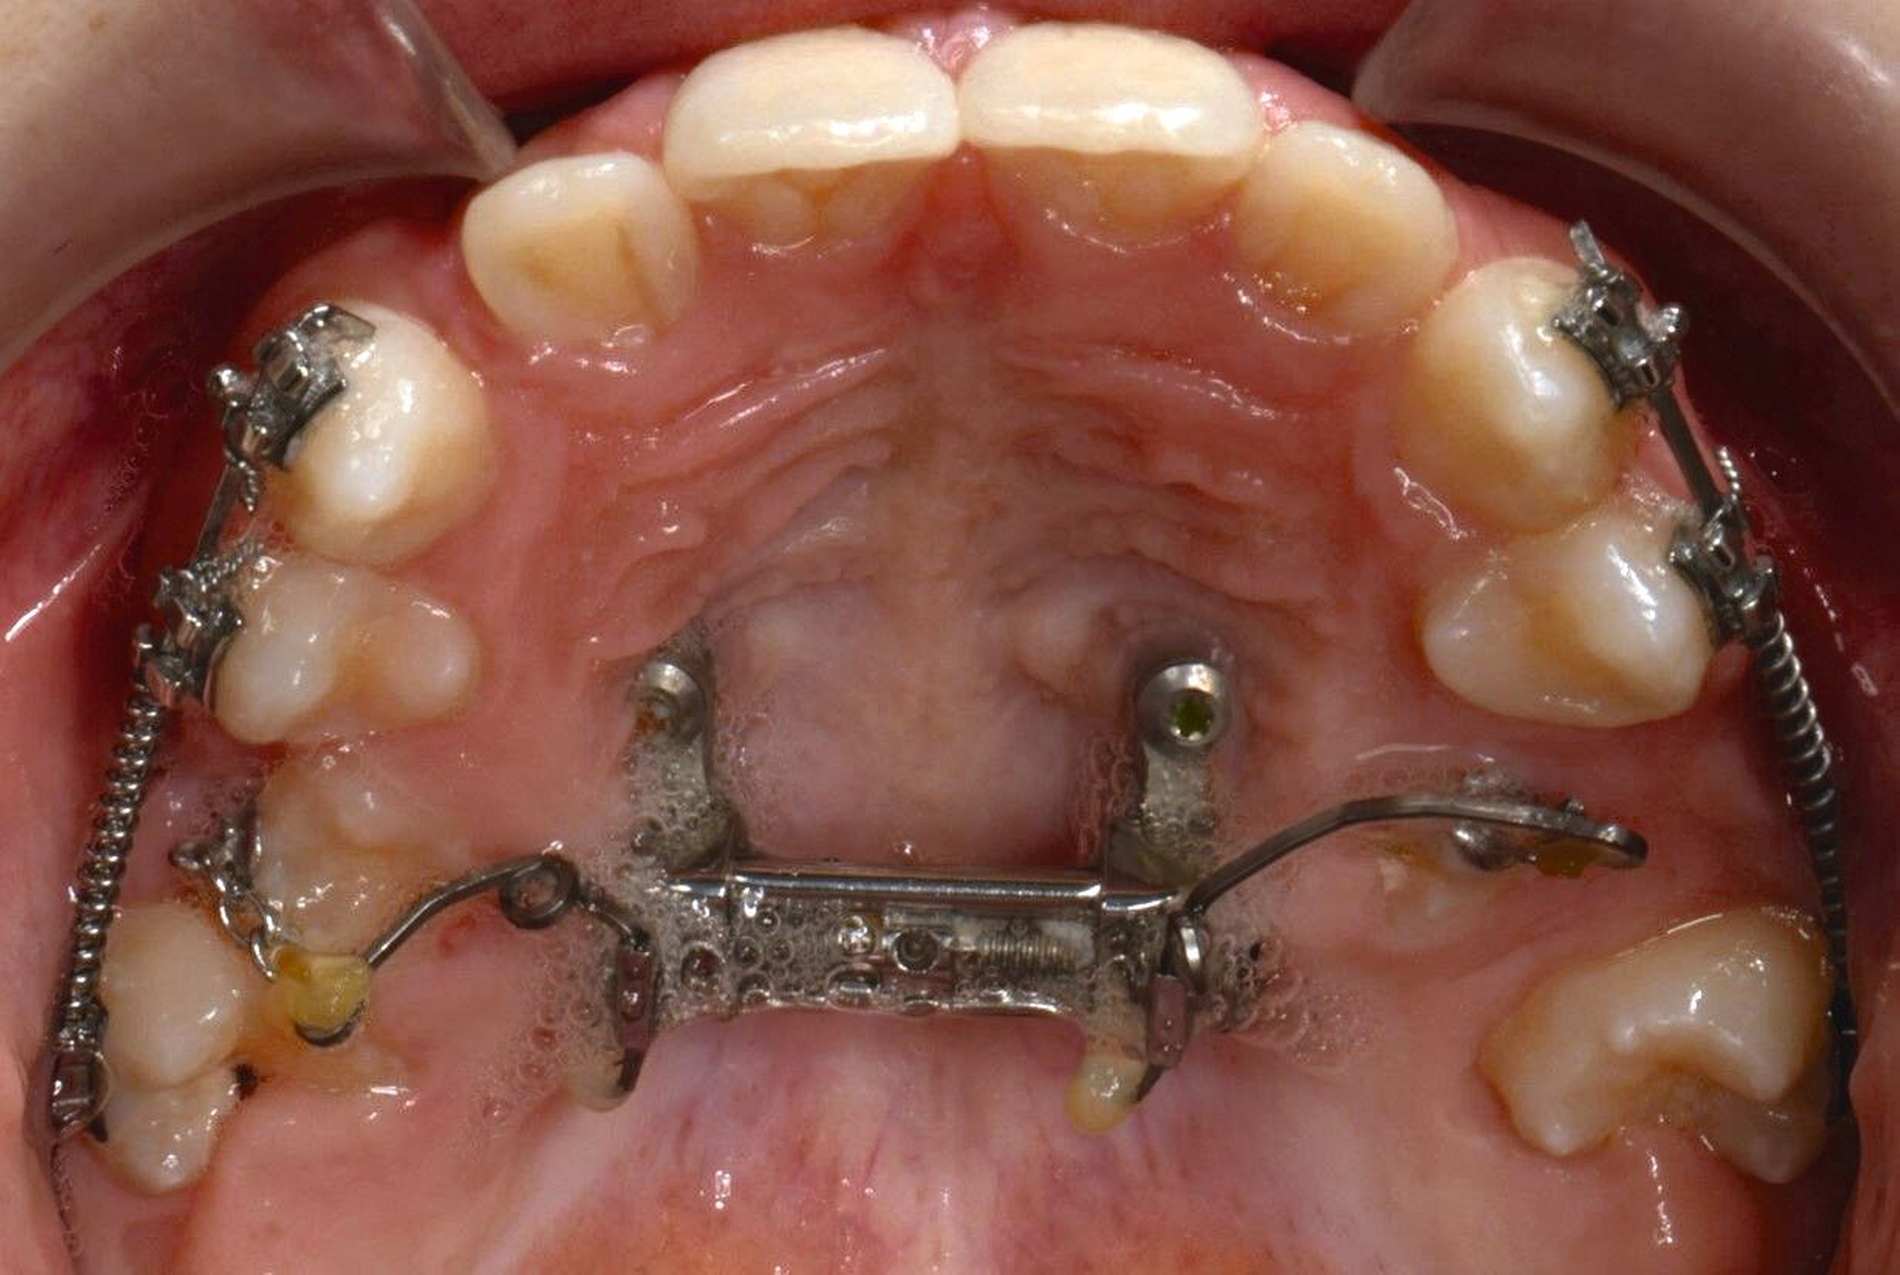

Die Eltern des Patienten wurden angewiesen, die Schraube einmal täglich zu aktivieren. Die gesamte Aktivierungszeit der Hyrax-Schraube betrug circa zehn Wochen. Während dieser Zeit vergrößerte sich die transversale Dimension des Oberkiefers um sieben Millimeter im posterioren Bereich (Milchmolaren) und um fünf Millimeter im anterioren Bereich (Milcheckzähne). Währenddessen trat ein mediales Diastema auf (Abbildungen 4b und 4c), das auf eine skelettale transversale Expansion des Oberkieferknochens hinwies. Nach der aktiven Expansionsphase der Hyrax-Apparatur wurde das Gerät für weitere Behandlungszwecke verwendet: Erstens als Retentionsgerät, um die bereits erzielte transversale Oberkieferbreite zu halten und zweitens als skelettal verankerte Apparatur zum Einstellen der retinierten und verlagerten Zähne mithilfe individuell angefertigter Kragarme. Hierfür wurde die Hyrax-Apparatur im zahntechnischen Labor modifiziert, indem Kreuzröhrchen für eine stationäre Befestigungen für die Drähte des Kragarms angebracht wurden.

Für die Zähne 13, 16, 23 und 26 wurde eine weitere chirurgische Freilegung durchgeführt. Zwei Kragarme (0,017 x 0,025 Zoll TMA-Draht, Dentaurum, Ispringen, Deutschland) wurden verwendet, um die Zähne 13 und 23 kieferorthopädisch in den Zahnbogen einzustellen. Danach wurde eine Teil-Multi-Bracket-Apparatur eingesetzt, um die eruptierten Zähne zu nivellieren (Abbildung 5b). Nach einer Behandlungsdauer von circa sechs Monaten waren die chirurgisch freigelegten Zähne optimal eingeordnet (Abbildungen 5c und 5d). Um die Lücke für die noch retinierten Prämolaren 15 und 25 zu öffnen, wurden in dieser Region auf den Teilbögen offene Federn angebracht. Danach wurden die Zähne 15 und 25 chirurgisch freigelegt und ebenfalls mithilfe von zwei Kragarmen (0,017 x 0,025 Zoll TMA-Draht) eingestellt (Abbildungen 5e und 5f, Abbildung 6).